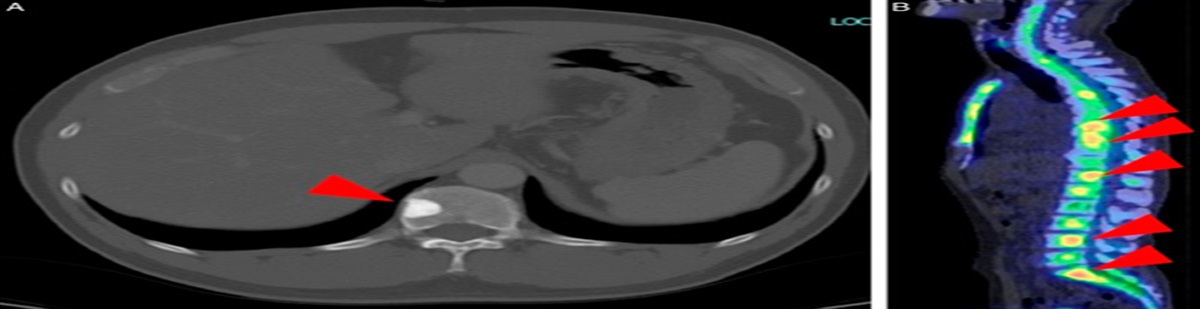

In July 2018, the patient had successfully delivered a term pregnancy without complications. The placenta was expelled but not sent for pathology review. After childbirth, on postpartum day 10, she experienced small amounts of vaginal bleeding that increased over the next few days. On postpartum day 40, the patient was transferred to the gynecological clinic. Physical examination showed an enlarged uterus (123×62 mm). Ultrasonography revealed an echogenic uterine mass (40×20×1.5 mm) with areas of necrosis and hemorrhage and hypervascular pattern on Doppler analysis. The blood hCG level was 500,000 mIU/mL. Compute tomography (CT) scan revealed solid nodular lesions (Fig. 1A) (>8) in both lungs, ranging from 10 to 22 mm in diameter. There was no evidence of brain or liver disease. In October 2018, the patient underwent biopsy of the uterine mass that confirmed the diagnosis of postpartum CCA. The patient was classified as having high-risk disease (stage III, score 9) based on FIGO staging and modified WHO risk-factor scoring system for gestational trophoblastic neoplasia. Therefore, first-line treatment with EMA-CO chemotherapy was given [Day 1: actinomycin-D 0.5 mg iv, etoposide 100 mg/m2 iv, methotrexate 300 mg/m2 iv. Day 2: actinomycin-D 0.5 mg iv, etoposide 100 mg/m2 iv, folinic acid 15 mg post 12 hourly for 4 doses. Day 8: vincristine 0.8 mg/m2 (maximum 2 mg), cyclophosphamide 600 mg/m2], starting October 2018. Unfortunately, after day 8 of first cycle, the patient developed severe abdominal pain and bowel obstruction caused by a volvulus, complicated by severe intestinal necrosis. She underwent bowel resection and complete hystero-annessectomy as emergency surgery. The procedure was performed by resident surgeon.

Figure 1Figure 1:

Comparison of pulmonary lesions. A, Lung computed tomography before chemotherapy. B, Lung computed tomography 3 months after chemotherapy. C, Lung computed tomography 5 months after chemotherapy.

In March 2019, the CT scan showed a partial response (PR) to treatment (reduction of lung lesions); normal hCG levels (3 mIU/mL) were observed. After discussing with the patient, 4 more cycles were administered. In May 2019, the CT scan revealed a further lung response, with lower blood hCG levels (<0.05 mIU/mL). Chemotherapy was stopped and a short-term follow-up was begun, with the patient undergoing a CT scan and assessment of hCG blood levels every 3 months. At the latest follow-up, in February 2020, the CT scan detected a further size reduction of pulmonary lesions (Figs. 1B, C) (maximum diameter 2 mm), while blood hCG value was 1 mIU/mL.